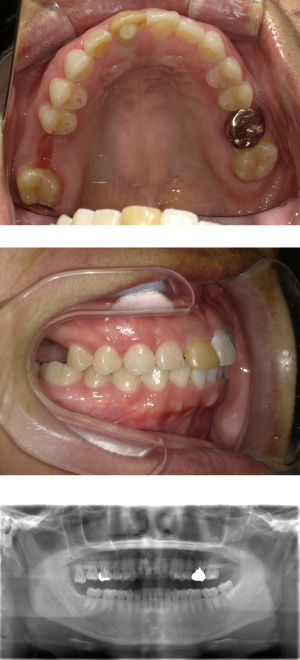

50代 女性 奥歯 インプラント ソケットリフト

| 年代・性別 | 50代・女性 |

| 主訴 | むし歯で右上を抜歯した後、左ばかりで咬むようになったので、右で咬めるようになりたい。 |

| 部位 | 右上6 |

| 治療期間 | 約1年 |

| 費用 | ¥432,000(税込) |

| 副作用・リスク |